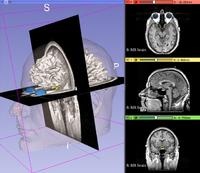

三维可视化

该图展示了如何使用3D Slicer加载DICOM图像,并进行三维可视化。